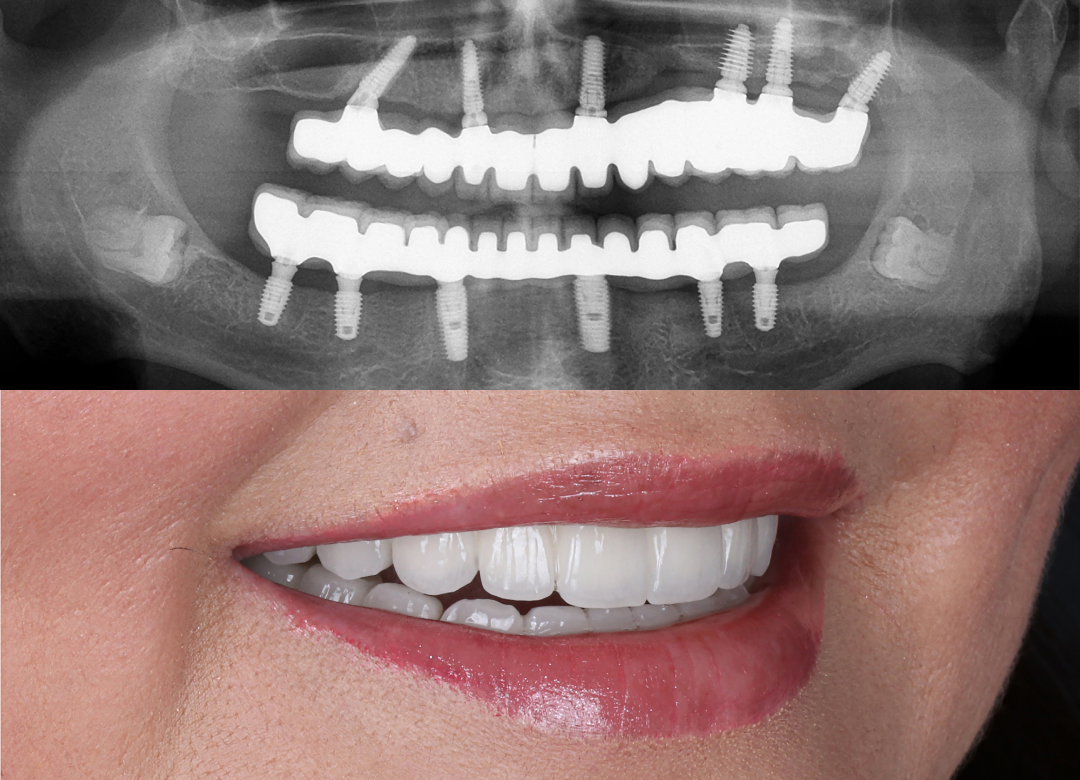

Before and After Gallery

Our before and after gallery highlights real results from patients who trusted us to restore function, comfort, and confidence through advanced, personalized dental care.